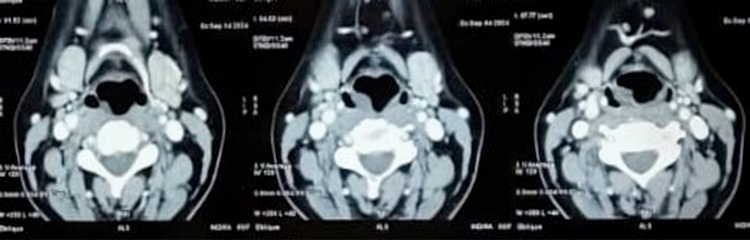

A CECT of the neck showed heterogeneously enhancing soft tissue lesions in the supraglottic and glottis regions with no evidence of calcification, necrosis, or regional lymphadenopathy (Figure 2).

Figure 2. CECT Neck showing heterogeneously enhancing soft tissue lesions in the supraglottis and glottis